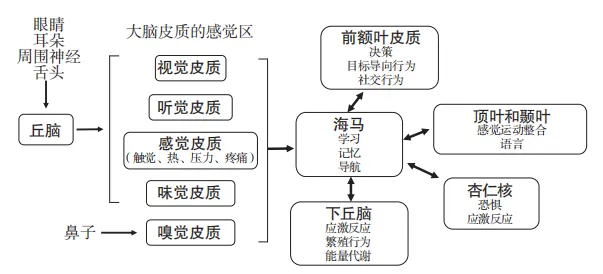

谷氨酸是一种重要的兴奋性神经递质,参与了我们对外界的感知、记忆的存储、情绪的调节,它通过两条纹状体丘脑通路调节丘脑功能,直接或间接地影响我们的认知控制功能。

实际上,感官通路中的所有神经元都使用谷氨酸作为神经递质。

通过谷氨酸能通路,海马与前额叶皮质、顶叶、颞叶、杏仁核和下丘脑相互连接,完成学习、记忆、空间导航和认知地图构建等一系列“脑力劳动”。

额叶中的回路在工作记忆和情景记忆的存储中发挥着关键作用,而海马与额叶之间有很强的谷氨酸能联系。

在这一系列的过程中,海马负责将这个单词的一些基本信息(如读音、拼写等)进行编码,然后通过谷氨酸能通路将信号传递给额叶。

额叶接收到这些信号后,会对信息进行进一步的加工处理,这个过程依赖于谷氨酸的兴奋性传递。